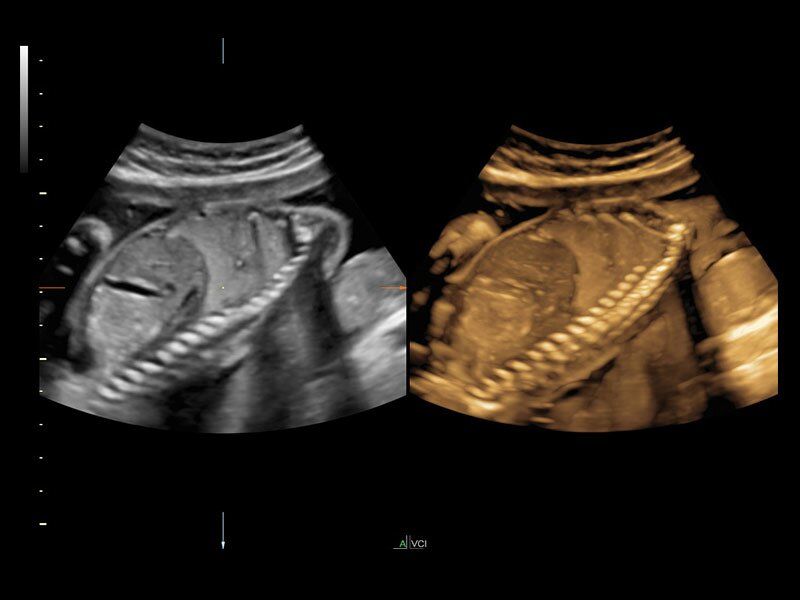

Клинические изображения

• Режим увеличенного разрешения и дифференциации тканей (HDres)

• Панорамное сканирование (XTD View)

• Многолучевое сложносоставное сканирование (CRI)

• Органоспецифичный режим подавления артефактов (SRI)

Четкие и подробные изображения

В медицинском учреждении, которое работает в условиях высокой нагрузки, значение имеет каждая минута. У врача нет времени подолгу корректировать параметры настройки, чтобы добиться наилучшей детализации изображения. Инновационная архитектура УЗИ аппарата Voluson E10 избавляет вас от лишних хлопот, — вы сразу получаете безукоризненную картинку. Вам не придется тратить лишнее время и силы: качество визуализации безупречно в любом режиме — от двумерных изображений до новейших 3D/4D технологий.

Современные клинические приложения и высокое качество изображений позволяют использовать Voluson E10 для наблюдения за ходом беременности максимально эффективно. С помощью этого аппарата можно проводить любые исследования, как рутинные, так и комплексные, выявляя проблемы на ранних стадиях и принимая своевременные меры.